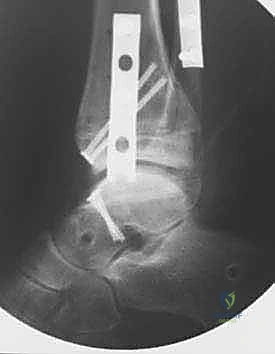

صور إضافية من داخل غرفة العمليات والخطوات الجراحية

ندرك أهمية توثيق الخطوات الجراحية لطلاب الطب والمرضى الراغبين في فهم دقة الإجراء. هذه الصور توضح مراحل زراعة وتثبيت الطعم العظمي الغضروفي بدقة متناهية تحت إشراف أ.د. محمد هطيف.